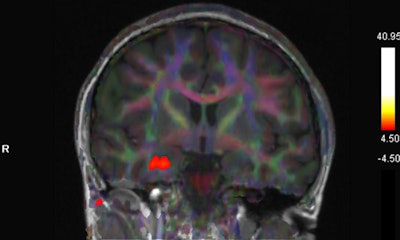

Blood oxygenation level-dependent (BOLD) activation on fMRI studies has been associated with olfactory sensation, a complex activity in the brain that involves the amygdala, the orbitofrontal cortex, and other structures, Gad and Ismail wrote.

"There is accumulating evidence of implication of OFC in patients with COVID-19 with olfactory dysfunction," they noted.

The patient in the case report experienced taste and smell dysfunction for three months and had been referred to a neurology clinic, where she had a normal examination. Clinicians performed a task-based functional MRI study that involved exposure to smells and the generation of BOLD activation maps. Activation was not seen in the orbitofrontal cortex, while there was a strong BOLD signal in the right uncus/piriform cortex, they reported.